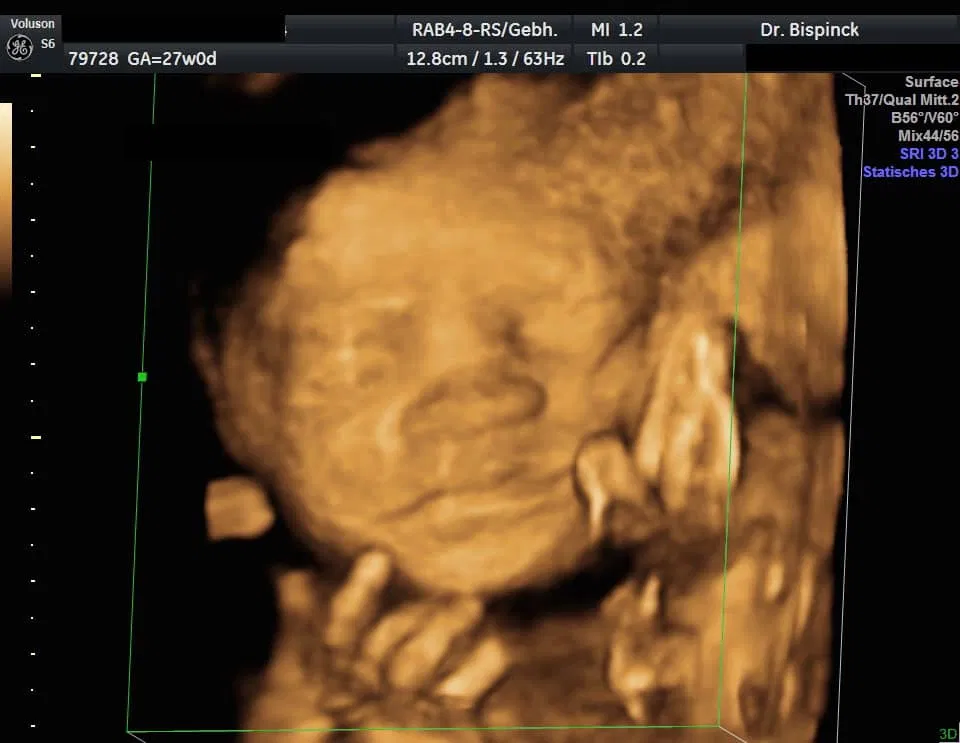

3D/4D Ultraschall

Gerne geben wir Ihnen Bildausdrucke mit.